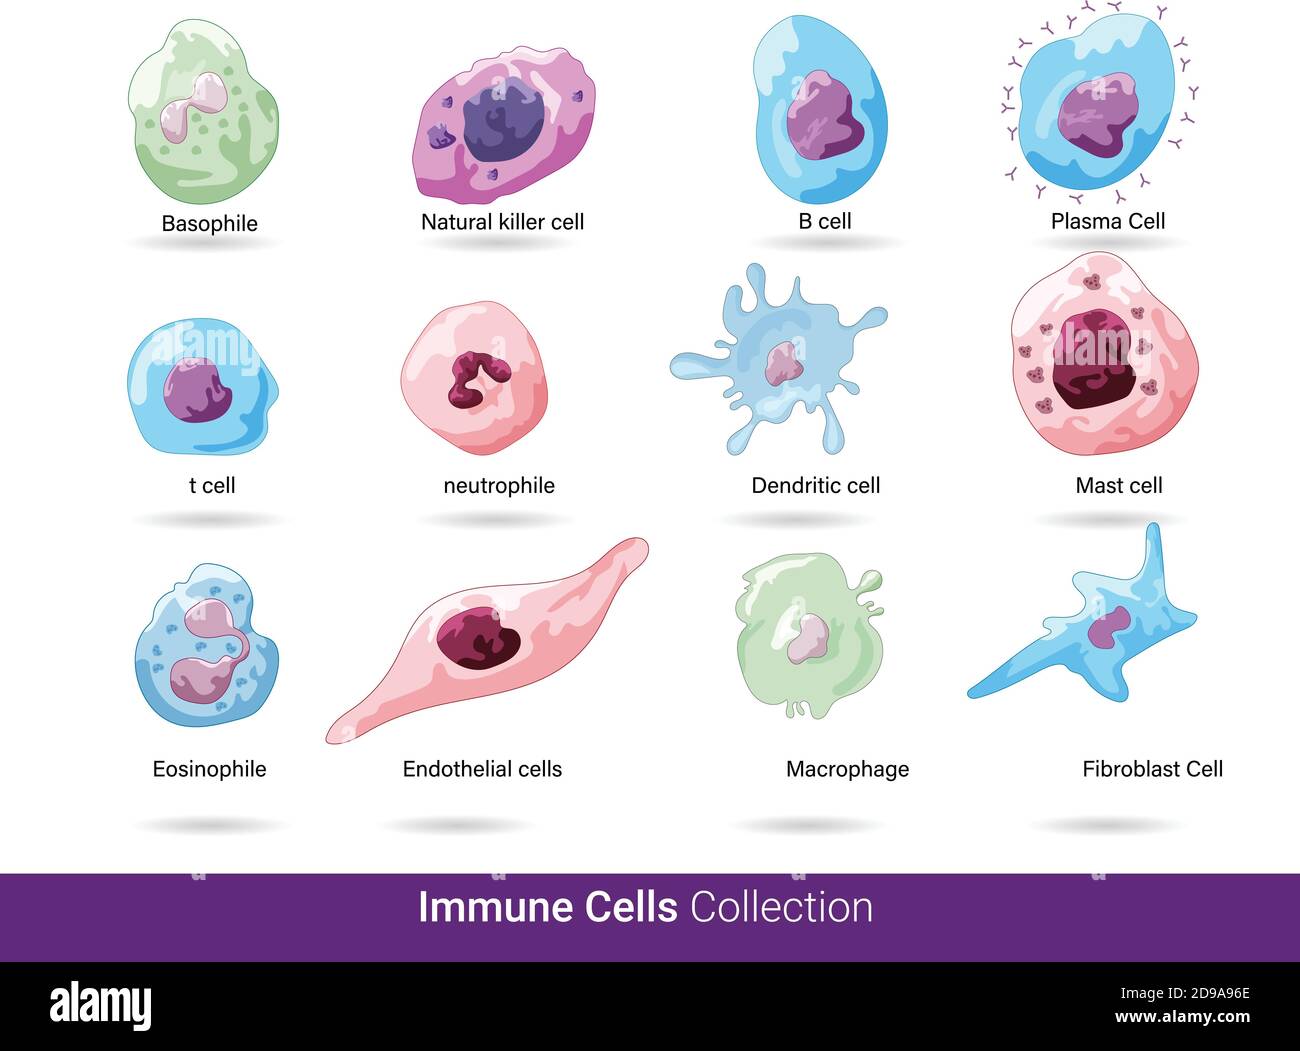

RF2D9A96E–Raccolta di tutte le 12 cellule immunitarie dell'uomo e sono cellule dendritiche, eosinofili, cellule killer naturali, cellule mast e b, t ed eosinofili